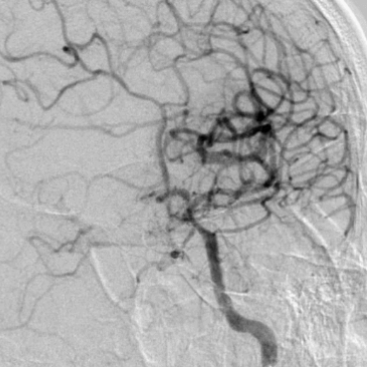

术前DSA

什么叫桡鞘【例久弥新】寻道于桡——瑞康通5.5F Introsky X导管鞘经桡取栓一例_https://www.jmylbn.com_新闻资讯_第8张

什么叫桡鞘【例久弥新】寻道于桡——瑞康通5.5F Introsky X导管鞘经桡取栓一例_https://www.jmylbn.com_新闻资讯_第9张